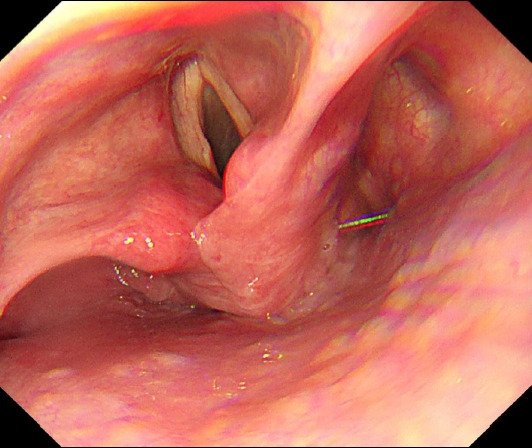

A 51-year-old man with a 10-day history of acute-onset dysphagia presented with inability to swallow anything orally. The patient was unable to swallow any radiopaque contrast medium; therefore, a videofluoroscopic swallow study could not be performed. Brain imaging, neurological findings, and initial endoscopy findings were normal. Neck computed tomography suggested left vocal cord paralysis. The patient was diagnosed with diabetes one year prior to presentation but did not receive any treatment. Insulin therapy during hospitalization controlled the patient's blood glucose levels, and his symptoms improved without any sequelae. We present a rare case of vocal cord paralysis secondary to controlled diabetes. The initial endoscopic examination did not include thorough evaluation of the vocal cords; therefore, accurate diagnosis was challenging in this case.

一名51岁男性,有10天急性发作吞咽困难病史,表现为无法口服任何东西。患者无法吞咽任何不透射线的造影剂;因此,无法进行视频透视吞咽研究。脑成像、神经系统检查结果和初步内窥镜检查结果均正常。颈部计算机断层扫描显示左声带麻痹。患者在就诊前一年被诊断为糖尿病,但未接受任何治疗。住院期间的胰岛素治疗控制了患者的血糖水平,症状得到改善,没有任何后遗症。我们报告了一例罕见的继发于控制性糖尿病的声带麻痹病例。最初的内窥镜检查不包括对声带的彻底评估;因此,在这种情况下,准确的诊断具有挑战性。